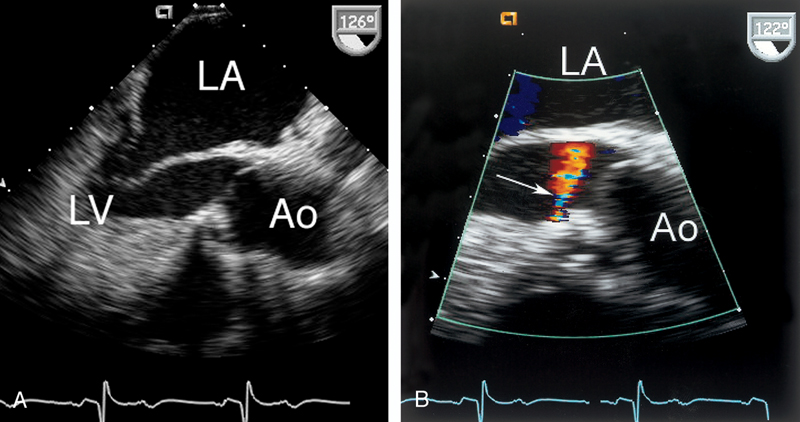

فحوصات تشخيصية لبعض امراض القلب والشرايين التاجية